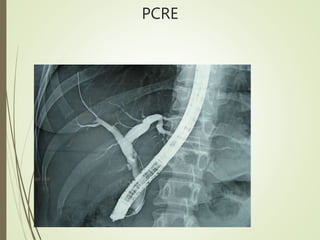

PANCREATOCOLANGIOGRAFIA

RETRÓGRADA ENDOSCÓPICA.

ESFINTERECTOMÍA ENDOSCÓPICA:

-PCRE terapéutica urgente: P.A severa de origen biliar sospechado o

probado.

-Es mejor realizarlo dentro de las primeras 72 hrs.

-Cuando hay colangitis, ictericia o colédoco dilatado.

- EN PAG biliar se debe realizar esfinterotomía se encuentre o no

cálculos en ella.

PCRE

PANCREATOCOLANGIOGRAFIA RETRÓGRADA ENDOSCÓPICA. ESFINTERECTOMÍA ENDOSCÓPICA: -PCREterapéutica urgente: P.A severa de origen biliar sospechado o probado. -Es mejor realizarlo dentro de las primeras 72 hrs. -Cuando hay colangitis, ictericia o colédoco dilatado. - EN PAG biliar se debe realizar esfinterotomía se encuentre o no cálculos en ella.